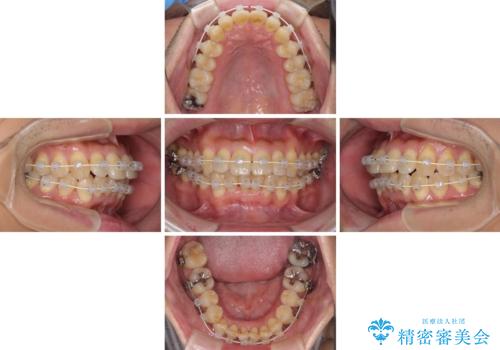

治療開始の頃は、食事や歯磨きが慣れず、装置が頻繁に脱落しましたが、2,3ヶ月ほどで慣れ、その後は1年ほどで治療を終えることができました。

- 矯正装置

- 審美装置

- 治療期間

- 1年3ヶ月